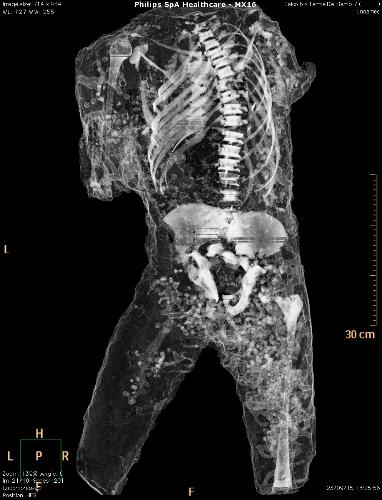

Por primera vez, un grupo de moldes de yeso de Pompeya ha sido sometido a tomografías axiales computerizadas (TAC), a partir de las que ha sido posible determinar la edad, las patologías médicas, los hábitos alimentarios y el estilo de vida de los habitantes de la ciudad arrasada por el Vesubio en el 79 d.C.

El objetivo del estudio radiológico ha sido obtener imágenes del interior de los cuerpos que quedaron conservados en ceniza durante la erupción del volcán, y que luego fueron rellenados con yeso con el propósito de preservar su integridad.

Asimismo, han sido realizados relieves en tres dimensiones de todos los cuerpos mediante técnicas digitales de vanguardia que permiten obtener datos sobre cómo ha variado su estado de conservación en el tiempo.